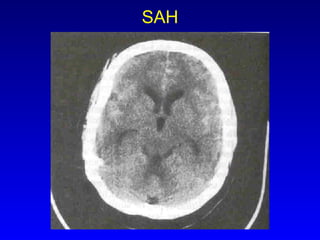

SAH

CT Vs MRI Preferred in SAH ICH Posterior fossa lesions CVT SDH, EDH Meningeal disease Cerebritis and abscess Pituitary pathology